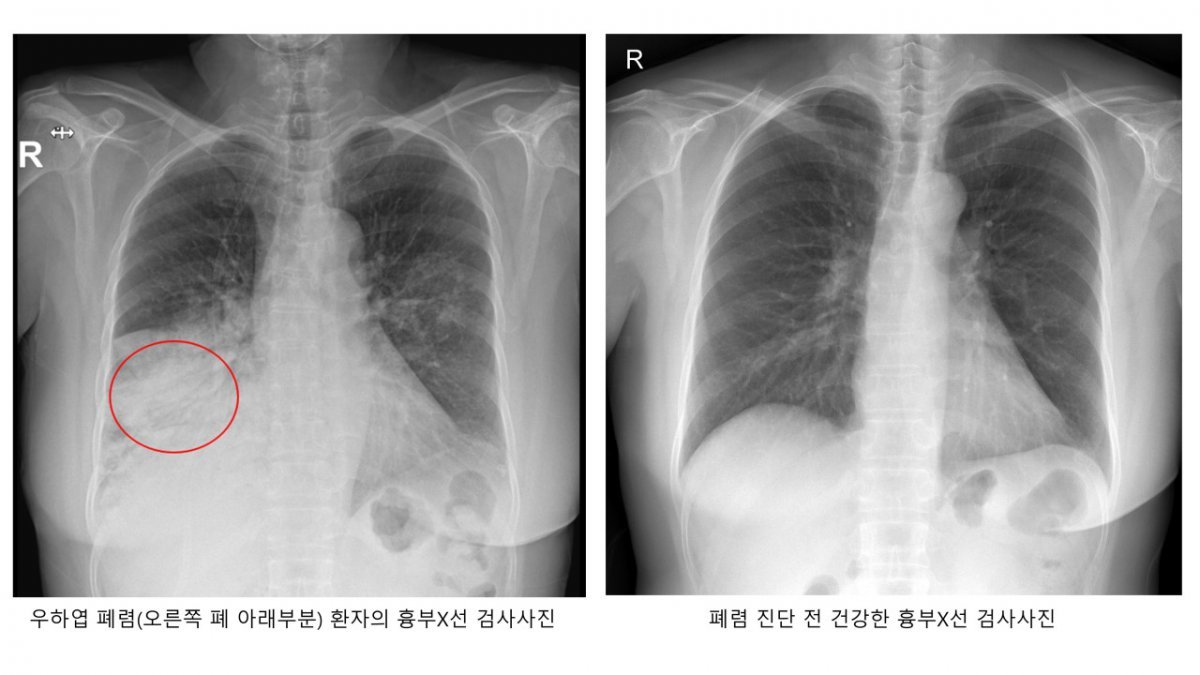

폐렴은 세균 또는 바이러스가 폐로 침투해 염증이 생긴 병이다. 폐렴구균으로 인한 세균성 폐렴이 흔하다. 폐렴구균은 평소에도 코와 목의 점막에 상주한다. 우리 몸의 면역력이 약해지면 폐, 뇌, 혈관, 귀까지 침투해서 폐렴, 수막염 등을 일으킨다.

폐렴의 초기 증상은 발열, 기침, 가래 등 일반 감기와 비슷하다. 하지만 폐렴구균이 본격적인 활동을 시작하면 고열과 기침, 가슴통증, 호흡곤란을 유발한다. 숨이 가빠지면 호흡수도 많아져 분당 20회를 초과한다.

폐렴구균이 원인인 폐렴일 경우 가래의 색깔이 적갈색으로 진하게 바뀌는 경우도 있다. 폐렴으로 인해 폐가 손상되게 되면 산소교환 기능이 저하되고, 혈액 속 산소 농도가 떨어진다.